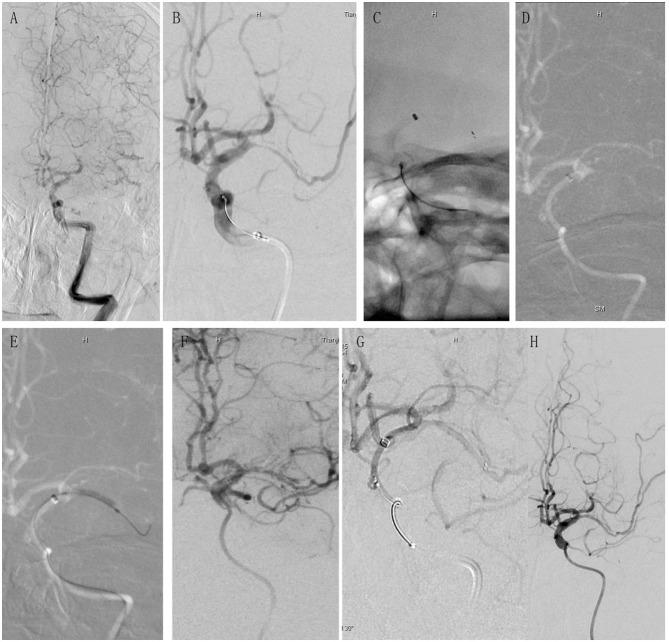

The retrograde semi-retrieval technique (RESET) has been described as a modified technique for endovascular thrombectomy (EVT) whose safety and efficacy for intracranial atherosclerosis stenosis (ICAS) patients remain uncertain. This article presents our single-center experience, comparing RESET vs. non-RESET in ICAS patients.

Compared to non-RESET, patients treated with RESET showed increased FPE incidence and significantly decreased puncture-to-reperfusion time. RESET was proven to be safe and effective in enhancing reperfusion for LVO patients receiving EVT with underlying ICAS.